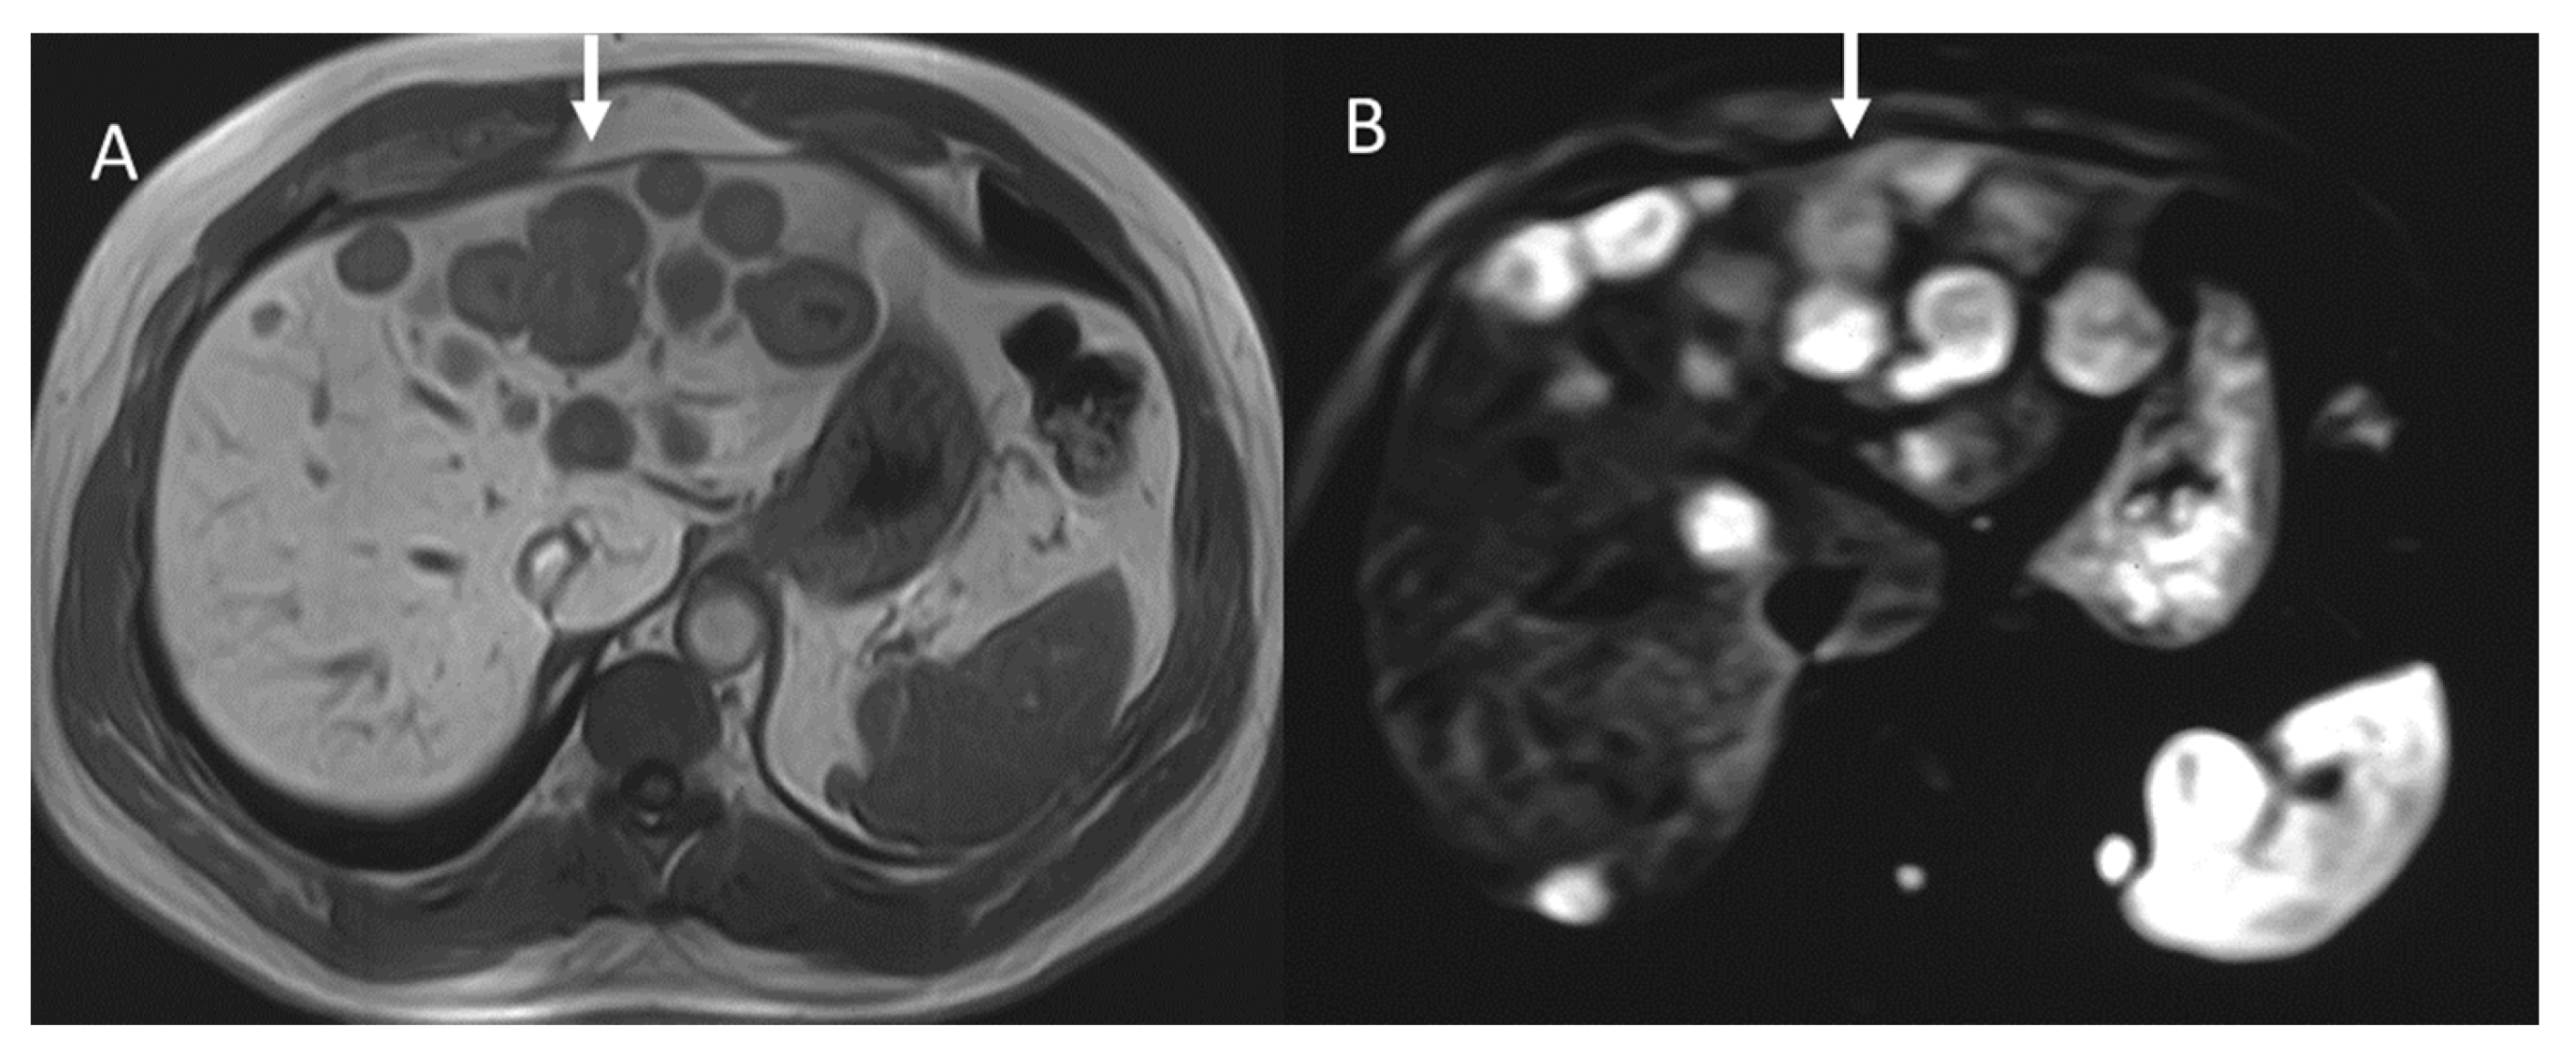

In contrast, in 68GaSSA PET/CT radiomics analysis, a higher entropy value resulted in a better association with PFS and OS, [120] in patients treated with PRRT. The entropy and kurtosis of the ADC were found to be higher in aggressive tumors, especially those with vascular invasion, lymph node disease, and liver metastases [98] (Figure 5). Although several parameters were significant for several aggressivity markers, kurtosis was found to be the best parameter in the identification of vascular invasion, showing an AUC of 0.763 using a cut-off value equal to 4.13, and in the identification of distant metastases, showing an AUC of 0.820 using a cut-off value of 3.64 [98].

Figure 5.

MRI evaluation of liver pNEN metastases. Morphological evaluation ((A): T1-W image) show hypointense lesions (arrow); in DWI ((B): b800 s/mm2), lesions show restricted signal.